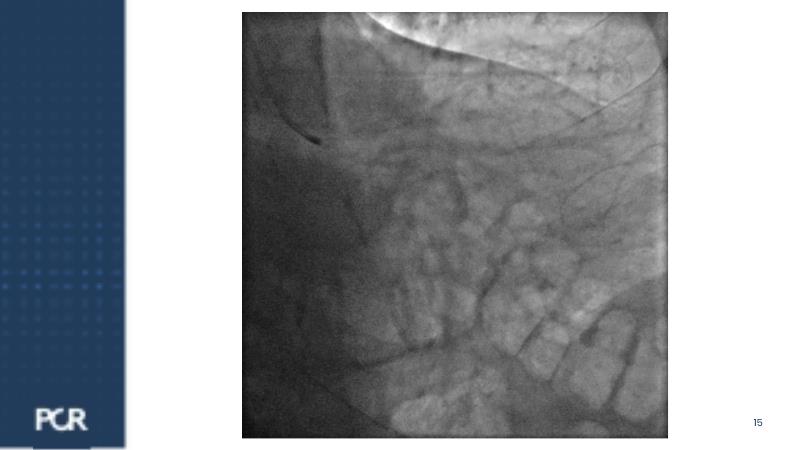

Watch this session for insights into managing acute coronary syndrome patients with multivessel disease, updates on treatment approaches, comparing FULL RESVAC with previous trials like COMPLETE or FIRE, for example, and information on ongoing trials such as FRAMI-AMI 2 and 3. Explore the LIVE case presentation for tailored strategies in post-ACS multivessel disease management, approaches for high bleeding risk patients, and the role of intracoronary imaging in guiding procedures.

- To analyse how intracoronary imaging optimises procedural outcomes of high bleeding risk patients